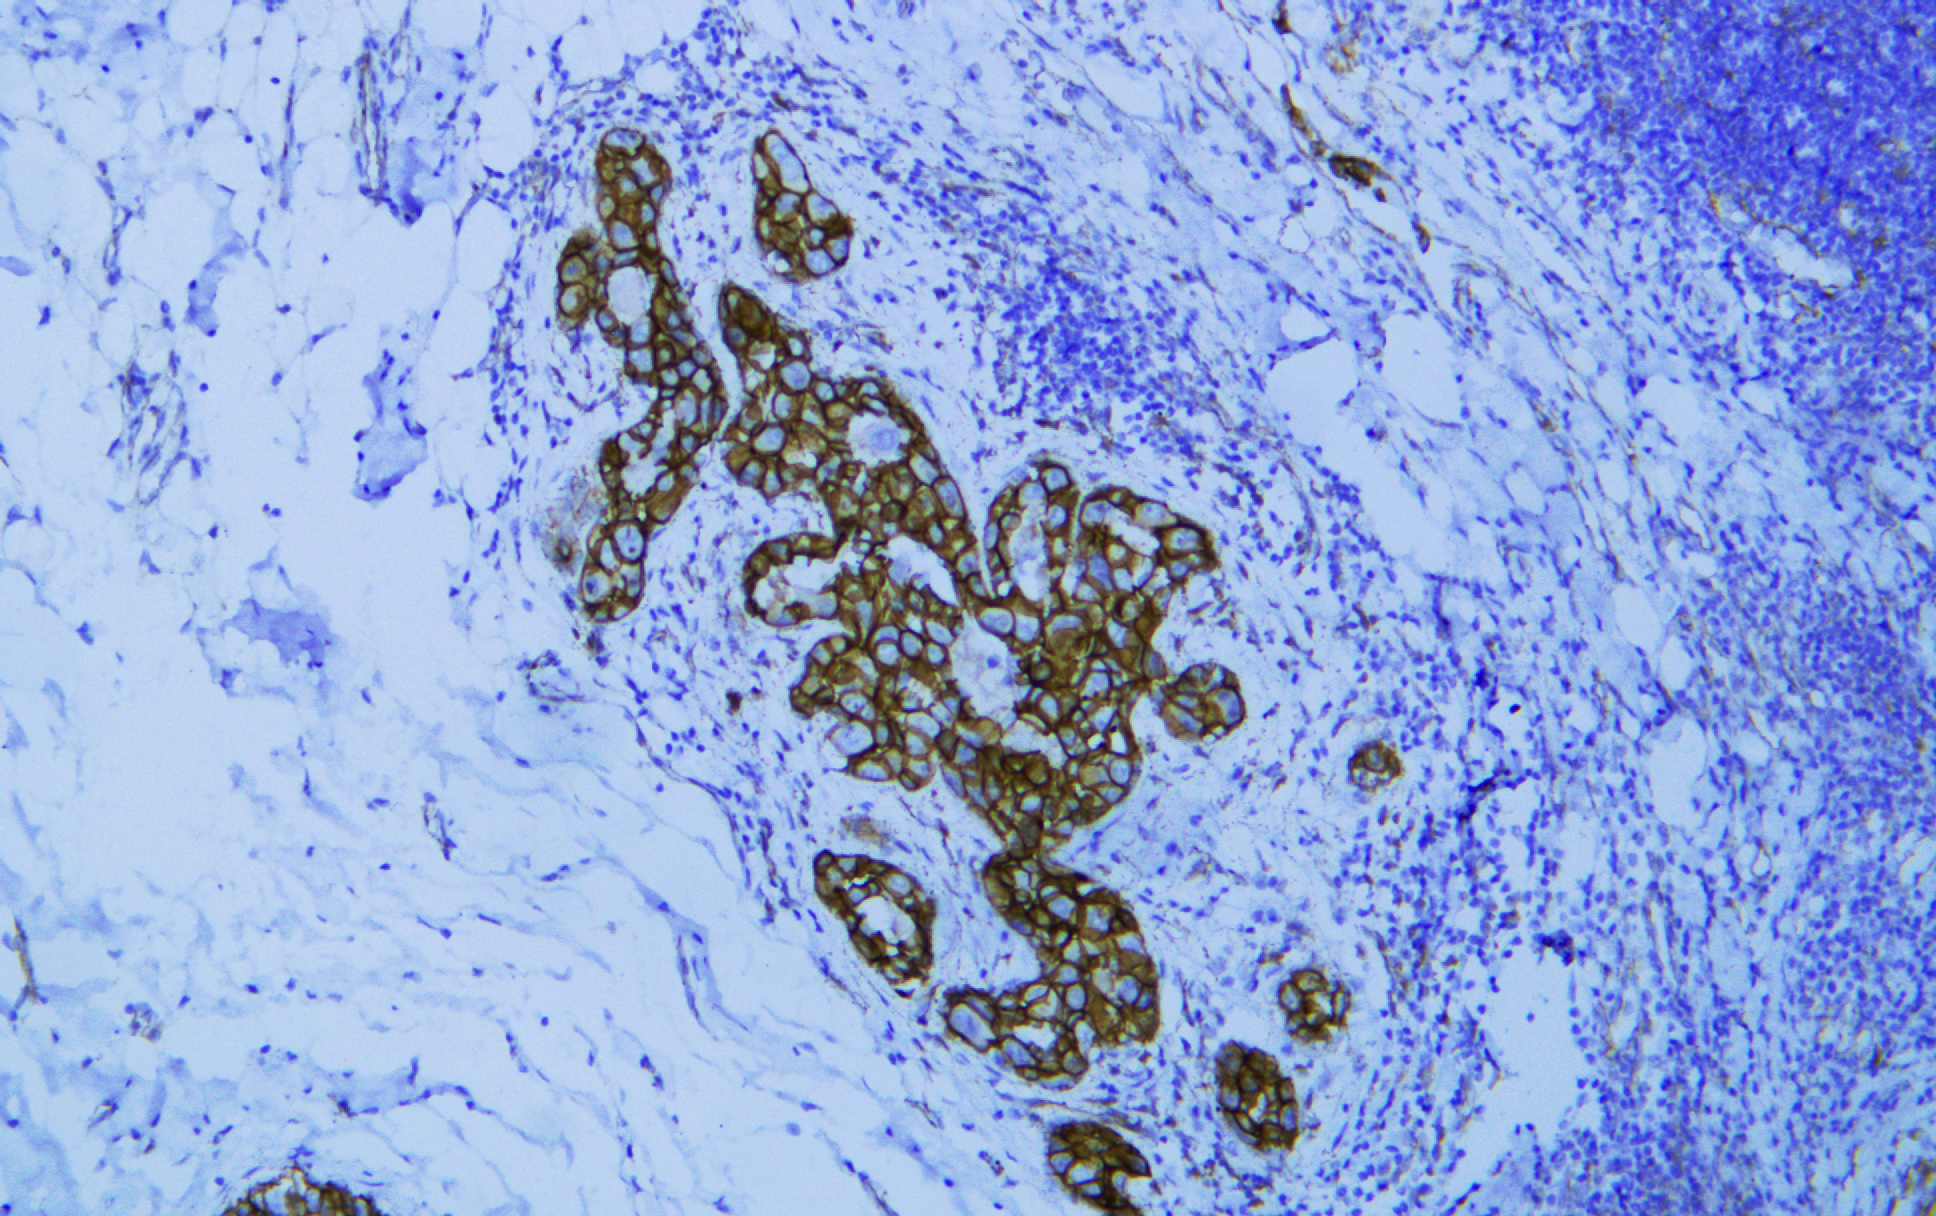

p120 catenin (AB1571) mouse mAb

Application:IHC; WB; IF; ELISA

α-Catenin、 β-Catenin、 γ-catenin and p120 catenin are members of the connexin family and mediate intercellular adhesion together with E-cadherin. P120 catenin binds to the near membrane region of E-cadherin to form a complex, which is stable and closely linked. In lobular breast cancer, E-cadherin deficiency resulted in the accumulation of p120 catenin in the cytoplasm, while in ductal breast cancer, p120 catenin in the membrane decreased and there was no accumulation of p120 catenin in the cytoplasm. Therefore, it can be used to distinguish lobular carcinoma from ductal carcinoma. Studies have shown that p120 catenin in the cytoplasm of gastric and colon cancer is related to poor adhesion of cancer cells.

IHC; WB; IF; ELISA

IHC, 1:200-1:1000 | WB, 1:500-1:2000 | IF, 1:100-1:500 | ELISA, Recommended starting concentration is 1 µg/mL. Please optimize the concentration based on your specific assay requirements.

The antibody can specifically recognize human p120 catenin protein. In western blotting of Hela, A431 and HEK293 cell lysates, the antibody can label a band with molecular weight around 100~110 kDa.